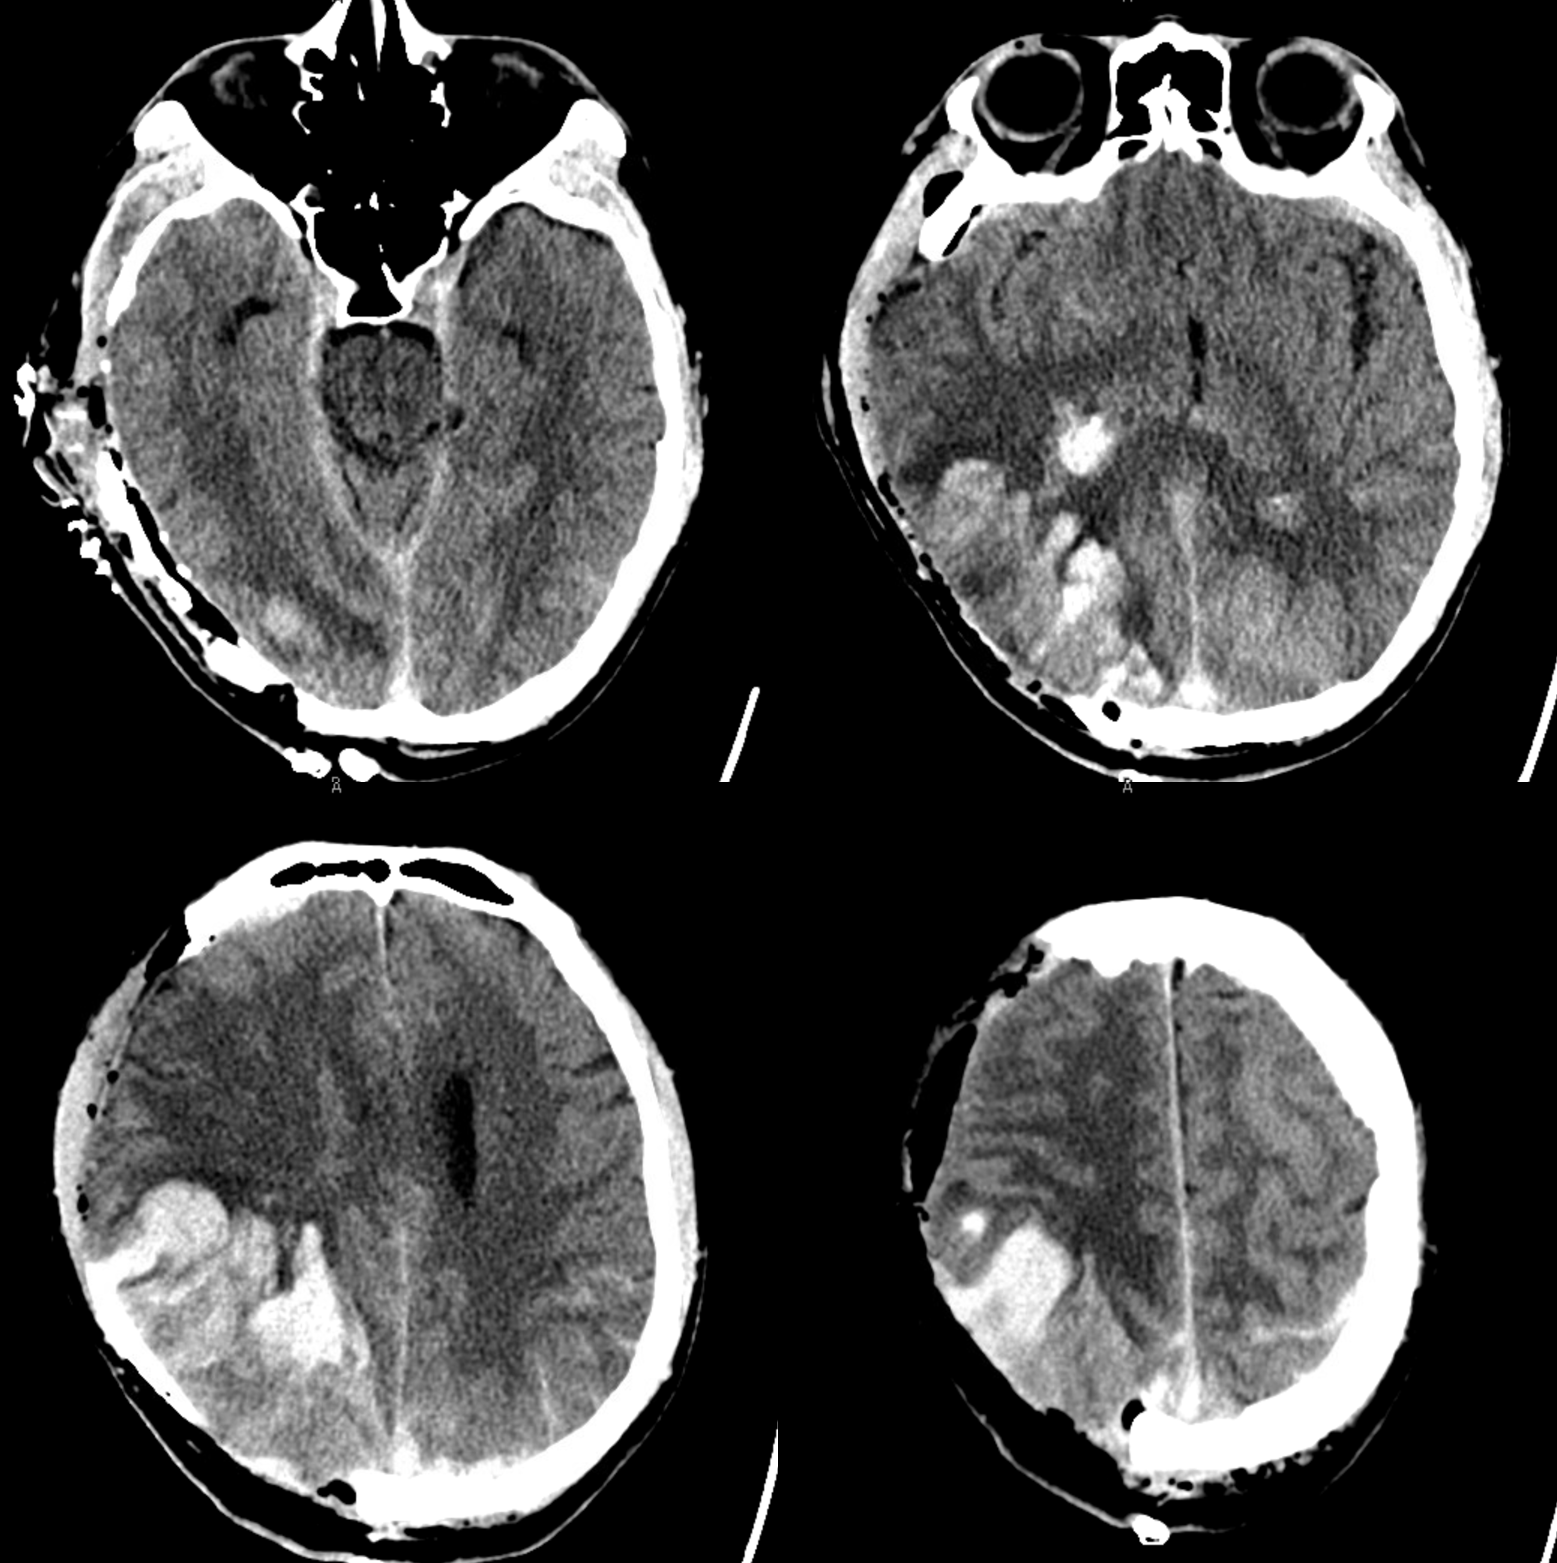

Below is a case of severe venous sinus thrombosis and secondary parenchymal venous infarcts

The explanation for the above tragic pattern is below. On the right, sigmoid and transverse sinuses are patent. However, the Labbe is hypoplastic, and majority of outflow used to go to the Trolard, into the now occluded SSS. There is no other effective way to go — the trolard tries to decompress via a left diploic vein, and convexity tries to access the deep venous system (which normally should not be well-seen in setting of hypoplastic right A1 segment). The left situation is much better, as well-developed superficial sylvian veins drain into the patent Cavernous Sinus. Thus, despite thrombosis of the left transverse and sigmoid sinuses, the left hemisphere is doing better, while the right one, which has patent transverse and sigmoid sinuses, is devastated.

Post venous thrombectomy — with limited results. Note presence of same left diploic vein as seen in right ICA injection, and connection between the distal superior sagittal sinus and the deep venous system via the inferior sagittal sinus.

Sagittal Sinus Thrombosis — collaterals.

All of the above anatomic knowledge can become very useful in evaluation of venous thrombosis. Numerous collateral pathways develop in this setting attempting to compensate for the loss. The most dramatic cases usually involve the largest channel — the superior sagittal sinus. In this case, a man presented with what initially was thought to be vasculitis-related brain hemorrhage. Subsequent workup led to an angiogram, where sagittal sinus thrombosis with extensive trans-cerebral and trans-osseous emissary vein collateral channels was seen. In retrospect, these findings were present on the patient’s earlier contrast MRI. “Venovibe” or other contrast-enhanced MR venograms can very sensitive, particularly when interpreted with the appropriate index of suspicion. Noncontrast 2-D time of flight MRV I consider to be next to useless as a problem-solving technique. Any thin-slice postcontrast T1 study is vastly superior.